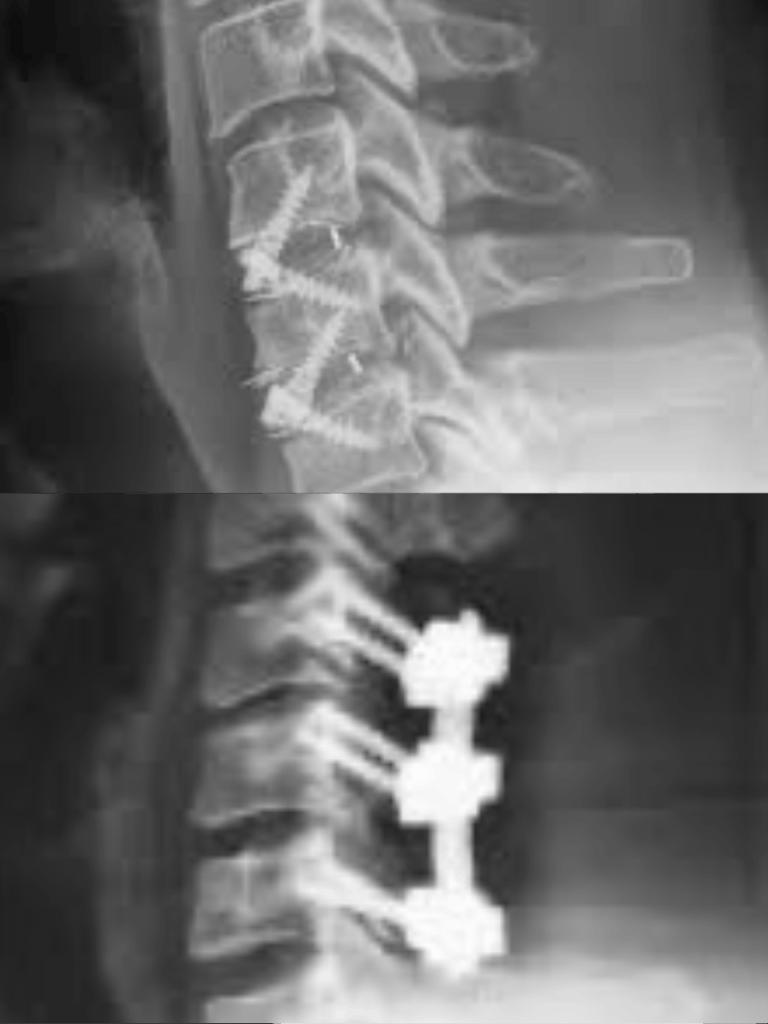

2. Fixation Techniques for Maximum Stability

Some conditions require stabilization to prevent further degeneration or nerve damage.

Dr. Sagar Kokate performs:

• Cervical Fusion Surgery

• Anterior Cervical Discectomy and Fusion (ACDF)

• Posterior Cervical Fixation

These techniques help correct instability, trauma, or severe disc collapse, ensuring proper alignment and long-term relief.